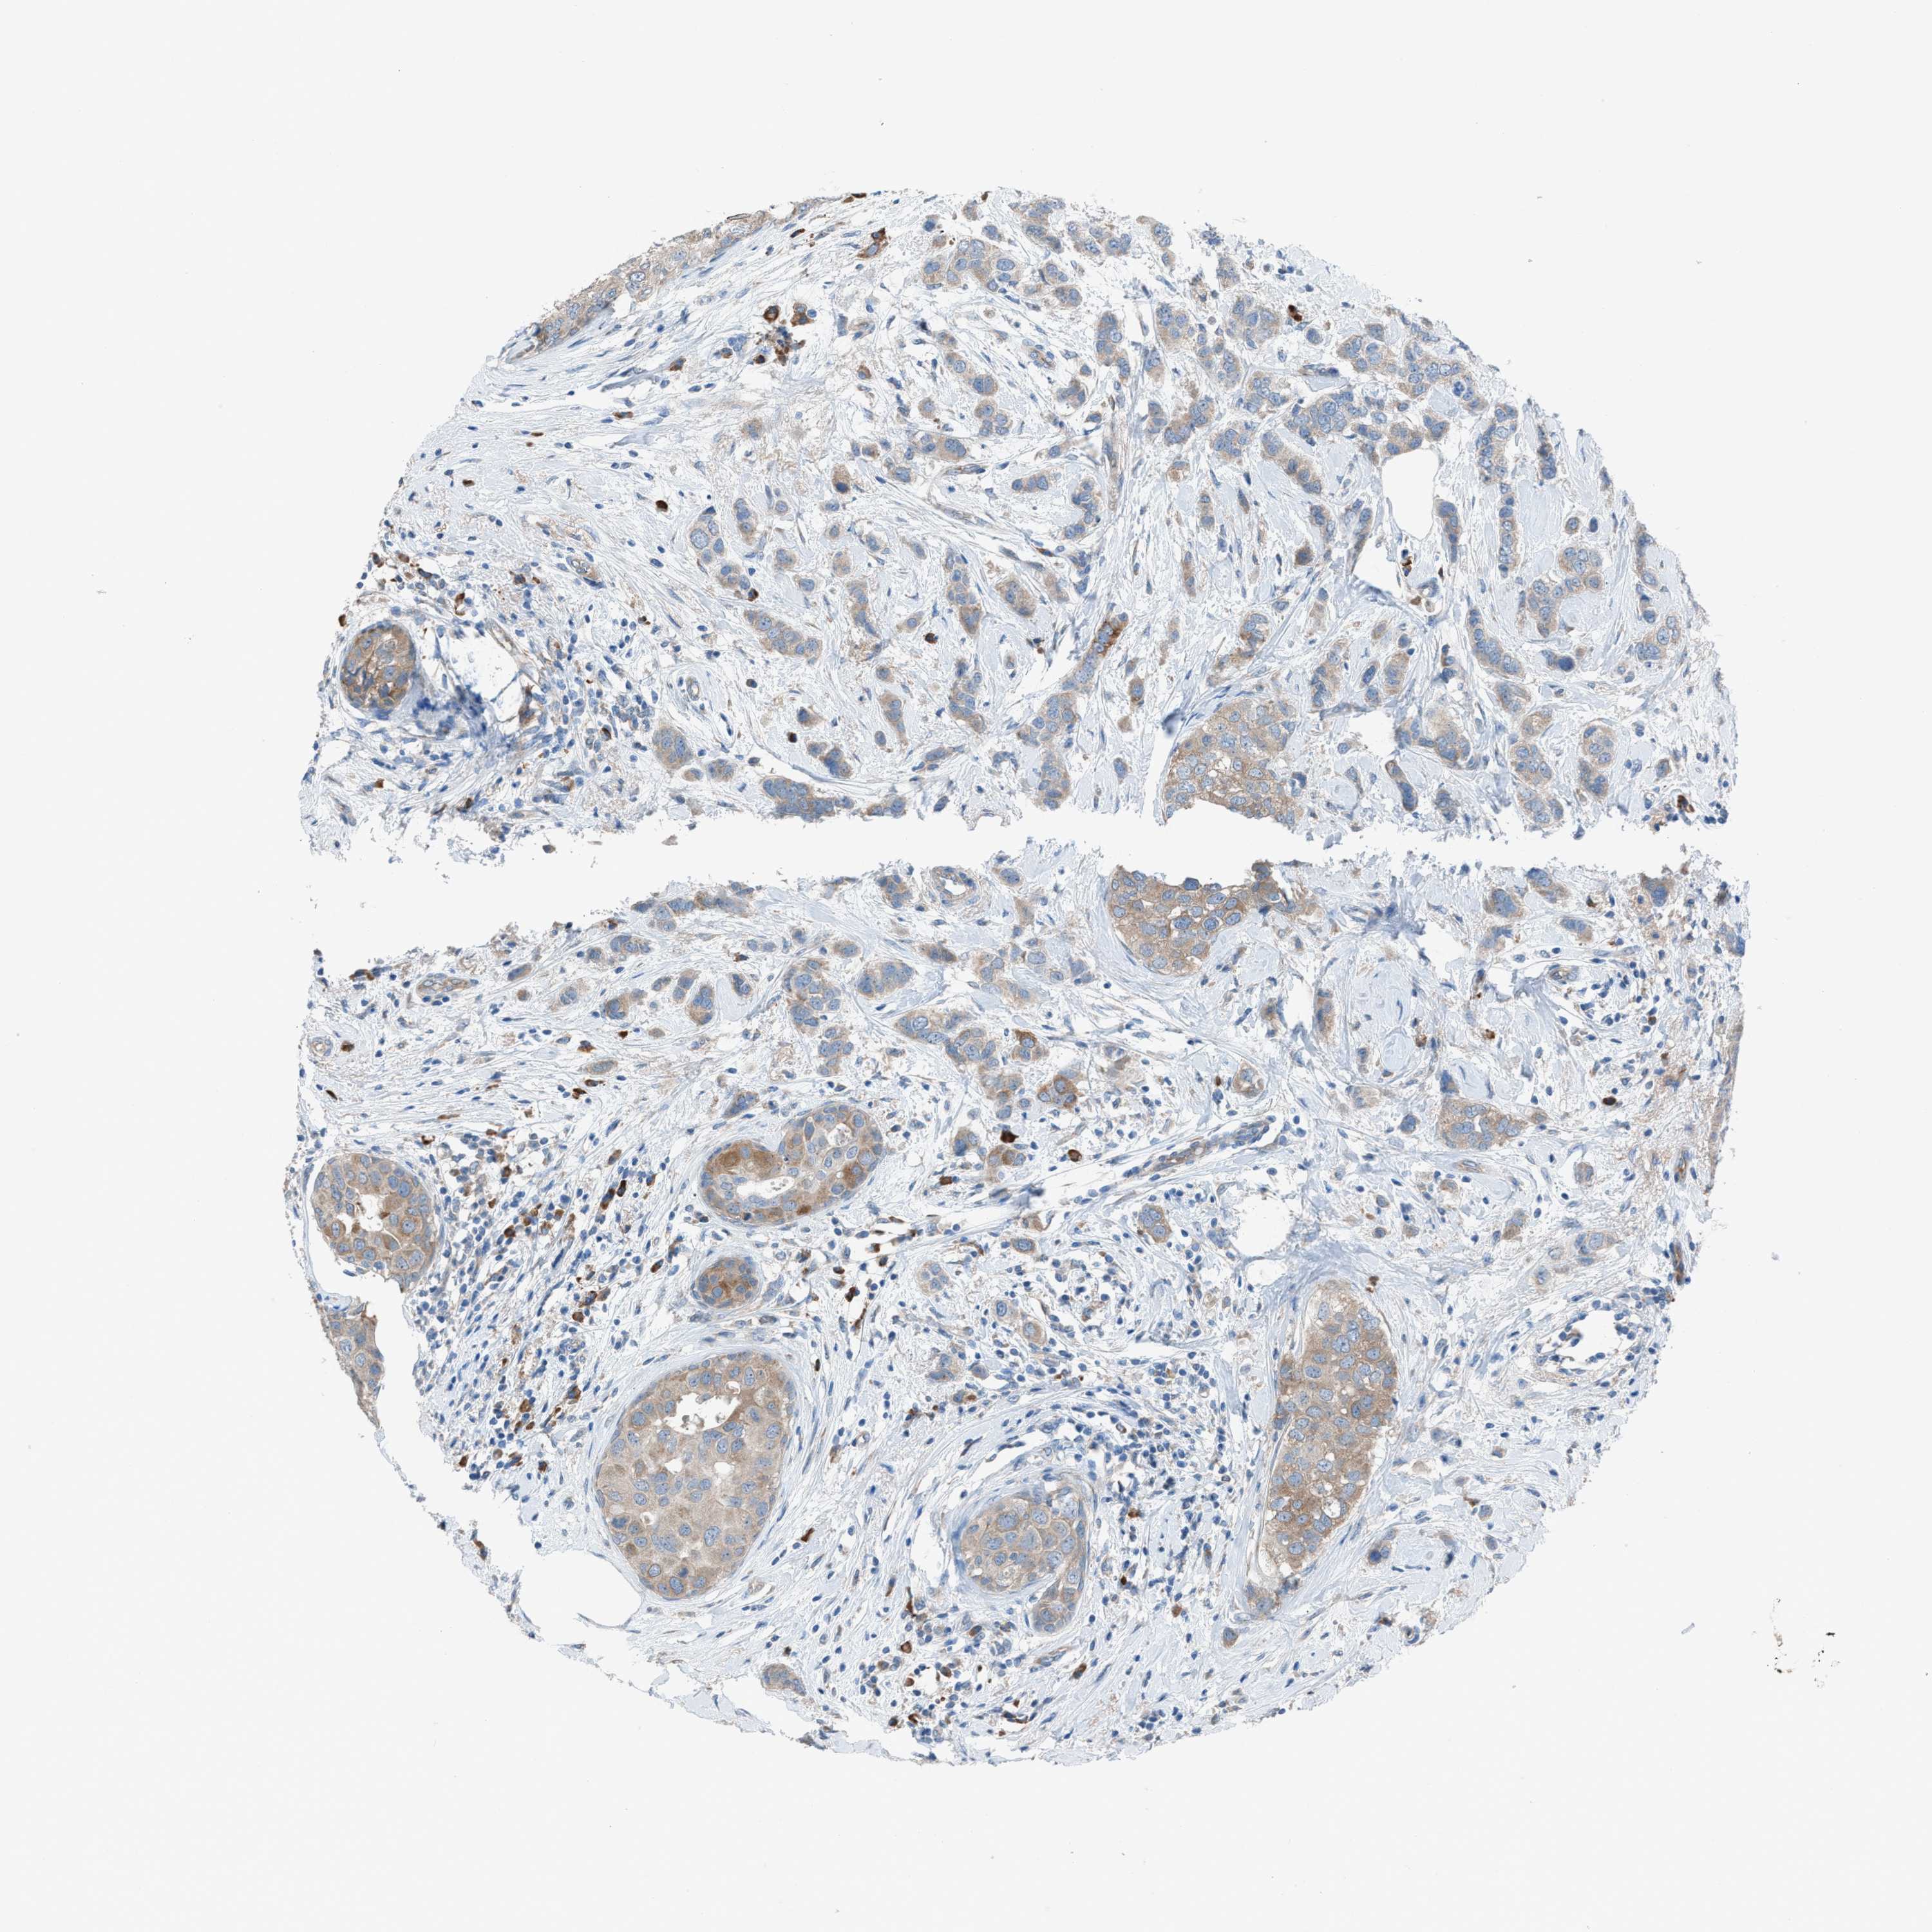

BRCA TCGA BRCA VALIDATION PROTEIN EXPRESSION

ANTIBODIES

AND

VALIDATION